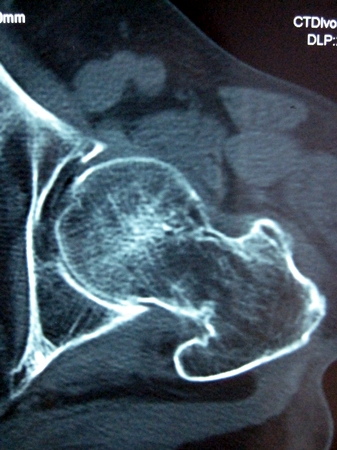

以下是引用lkc8963在2008-12-19 21:19:00的发言:[br]左?右?患侧大转子上移,股骨颈骨质浓杂,髋周见多发条片状骨化影,以小转子为著,多为陈旧性股骨颈骨折后改变并骨化性肌炎.请咨询既往史!